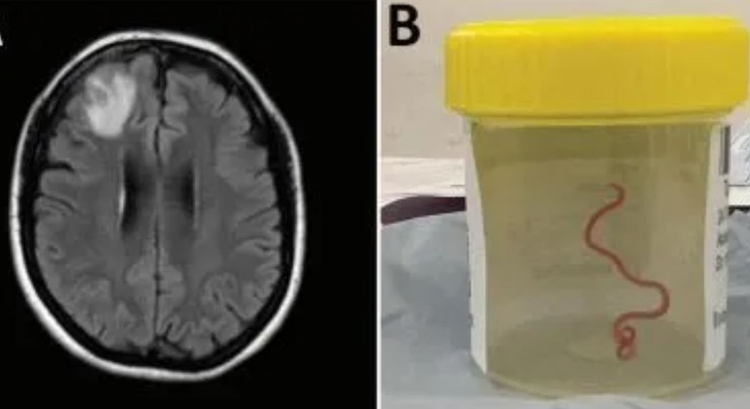

Médicos retiraram do cérebro de uma idosa de 64 anos, um verme de 8 cm que até hoje só era encontrado em cobras píton. O caso foi registrado na Austrália e divulgado em um artigo recente na revista Emerging Infectious Diseases.

Segundo os especialistas, a cirurgia de remoção acontece em junho de 2022, mas chamou a atenção dos pesquisadores por se tratar do primeiro caso em humanos.

O verme, da espécie Ophidascaris robertsi, foi retirado vivo e já estava no terceiro estágio de vida. Ele foi descoberto após a mulher apresentar perda de memória, febre, tosse e uma lesão grave no lobo frontal direito do cérebro, onde estava o verme.